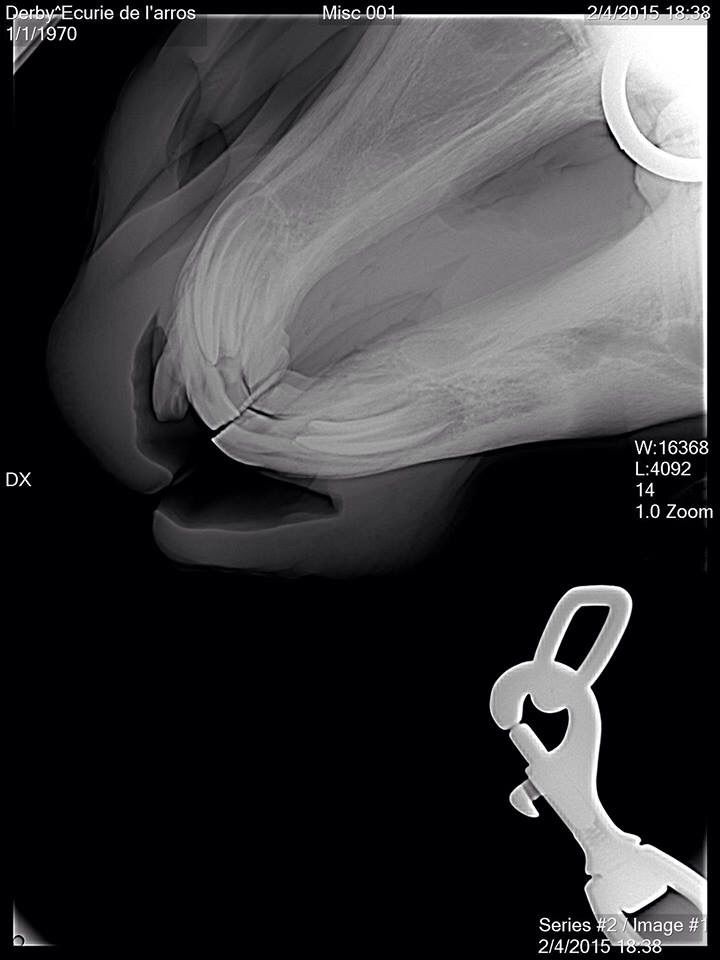

| Dire merci | Finalement on sera fixé demain après midi, la véto passe pour les radios, son associée pense à une fracture.... |

| Dire merci | oui sur tes photos ça en a vraiment la tronche. et c'est une malheureuse coincidence que ce soit après le passage de la dentiste, à moins qu'elle n'ait fait une énorme erreur, mais je vois vraiment pas comment elle aurait pu faire ça |

| Dire merci | Tout d abord desolee de ne pas vous avoir donné des nouvelles plus tôt . Le loulou va parfaitement bien, la dent etait bien fracturée, un cerclage a été réalise par l ecole veto de Nantes. Il est resté en place 6 semaines avant d être enlevé. Aujourdhui il est de nouveau au pré avec ses copains et tout va pour le mieux pour lui. Voici quelques photos: ![]() [/url] |

| Dire merci | Et une fois le cerclage réalisé, l intervention a duré 2 bonnes heures, le chirurgien a beaucoup gratté la gencive pour pouvoir remettre la dent à sa place. Le travail realisé est vraiment superbe, on ne se rend aujourdhui quasiment plus compte de ce qui lui est arrivé.![]() [/url] |

Pis faut voir le côté positif, t'as une superbe radio de ton mousqueton maintenant